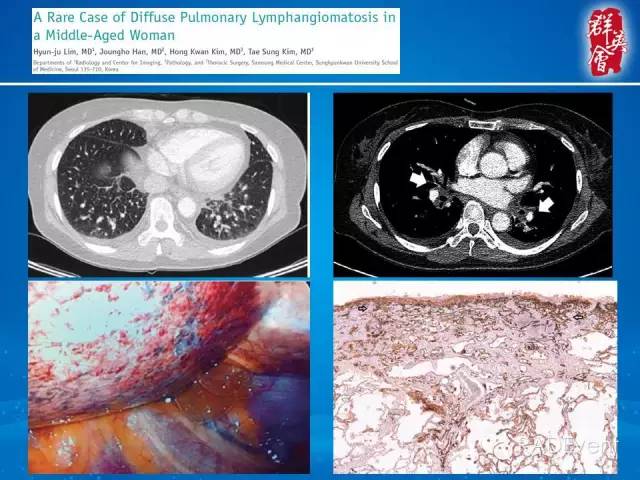

【病例】弥漫性肺淋巴管瘤病1例CT影像表现